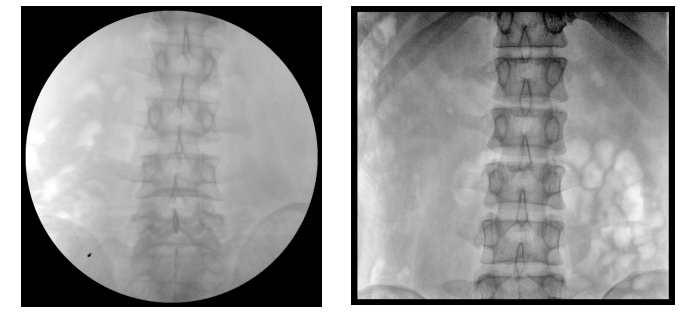

【產品臨床圖片】